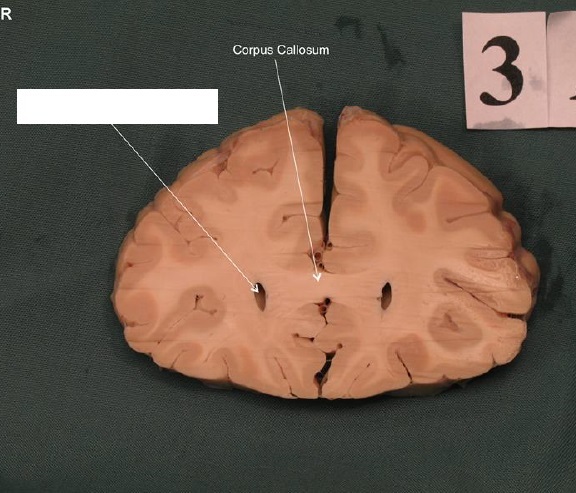

Genu of Corpus callosum

Lateral Ventricles